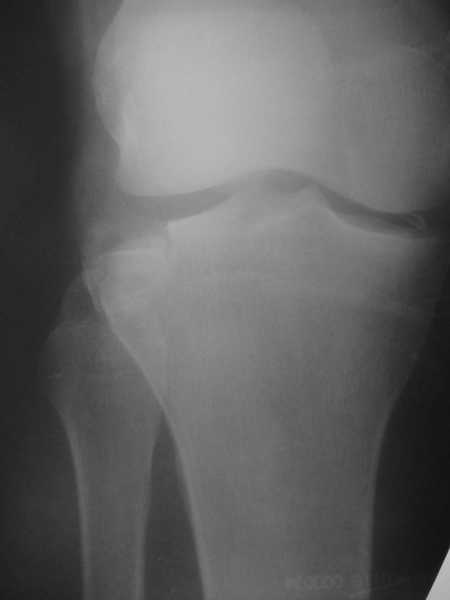

Прошу уважаемые форумчане помочь с проблемой. У друга перелом латерального мыщелка большеберцовой кости.

Травматологи ничего не говорят о тактике его лечения, а после беседы с врачом я так понял, что ее вовсе и нет. Сам я по специальности уролог и ничего не смыслю в вариантах лечения данной патологии но друг просит помочь. Снимок прилагаю

Наадо сделать КТ. И оперировать - надо восстанавливать форму суставной поверхности, т.е. поднять просевший мыщелок. Дефект заместить ауто- или алломатериалом. Фиксировать пластиной или аппаратом. Если в той больнице, где пациент сейчас, такие операции на потоке не делаются, то лучше перебраться куда-то в более продвинутое место.